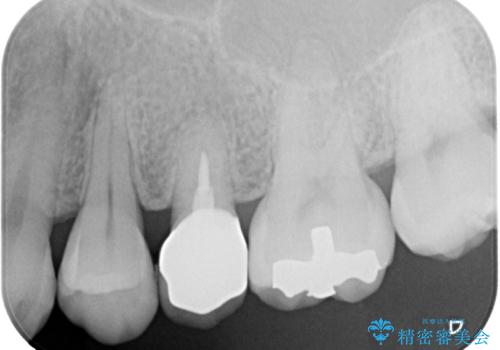

やはりむし歯は大きく、一部歯髄を切除することとなりましたが、その後は良好な経過をたどっています。